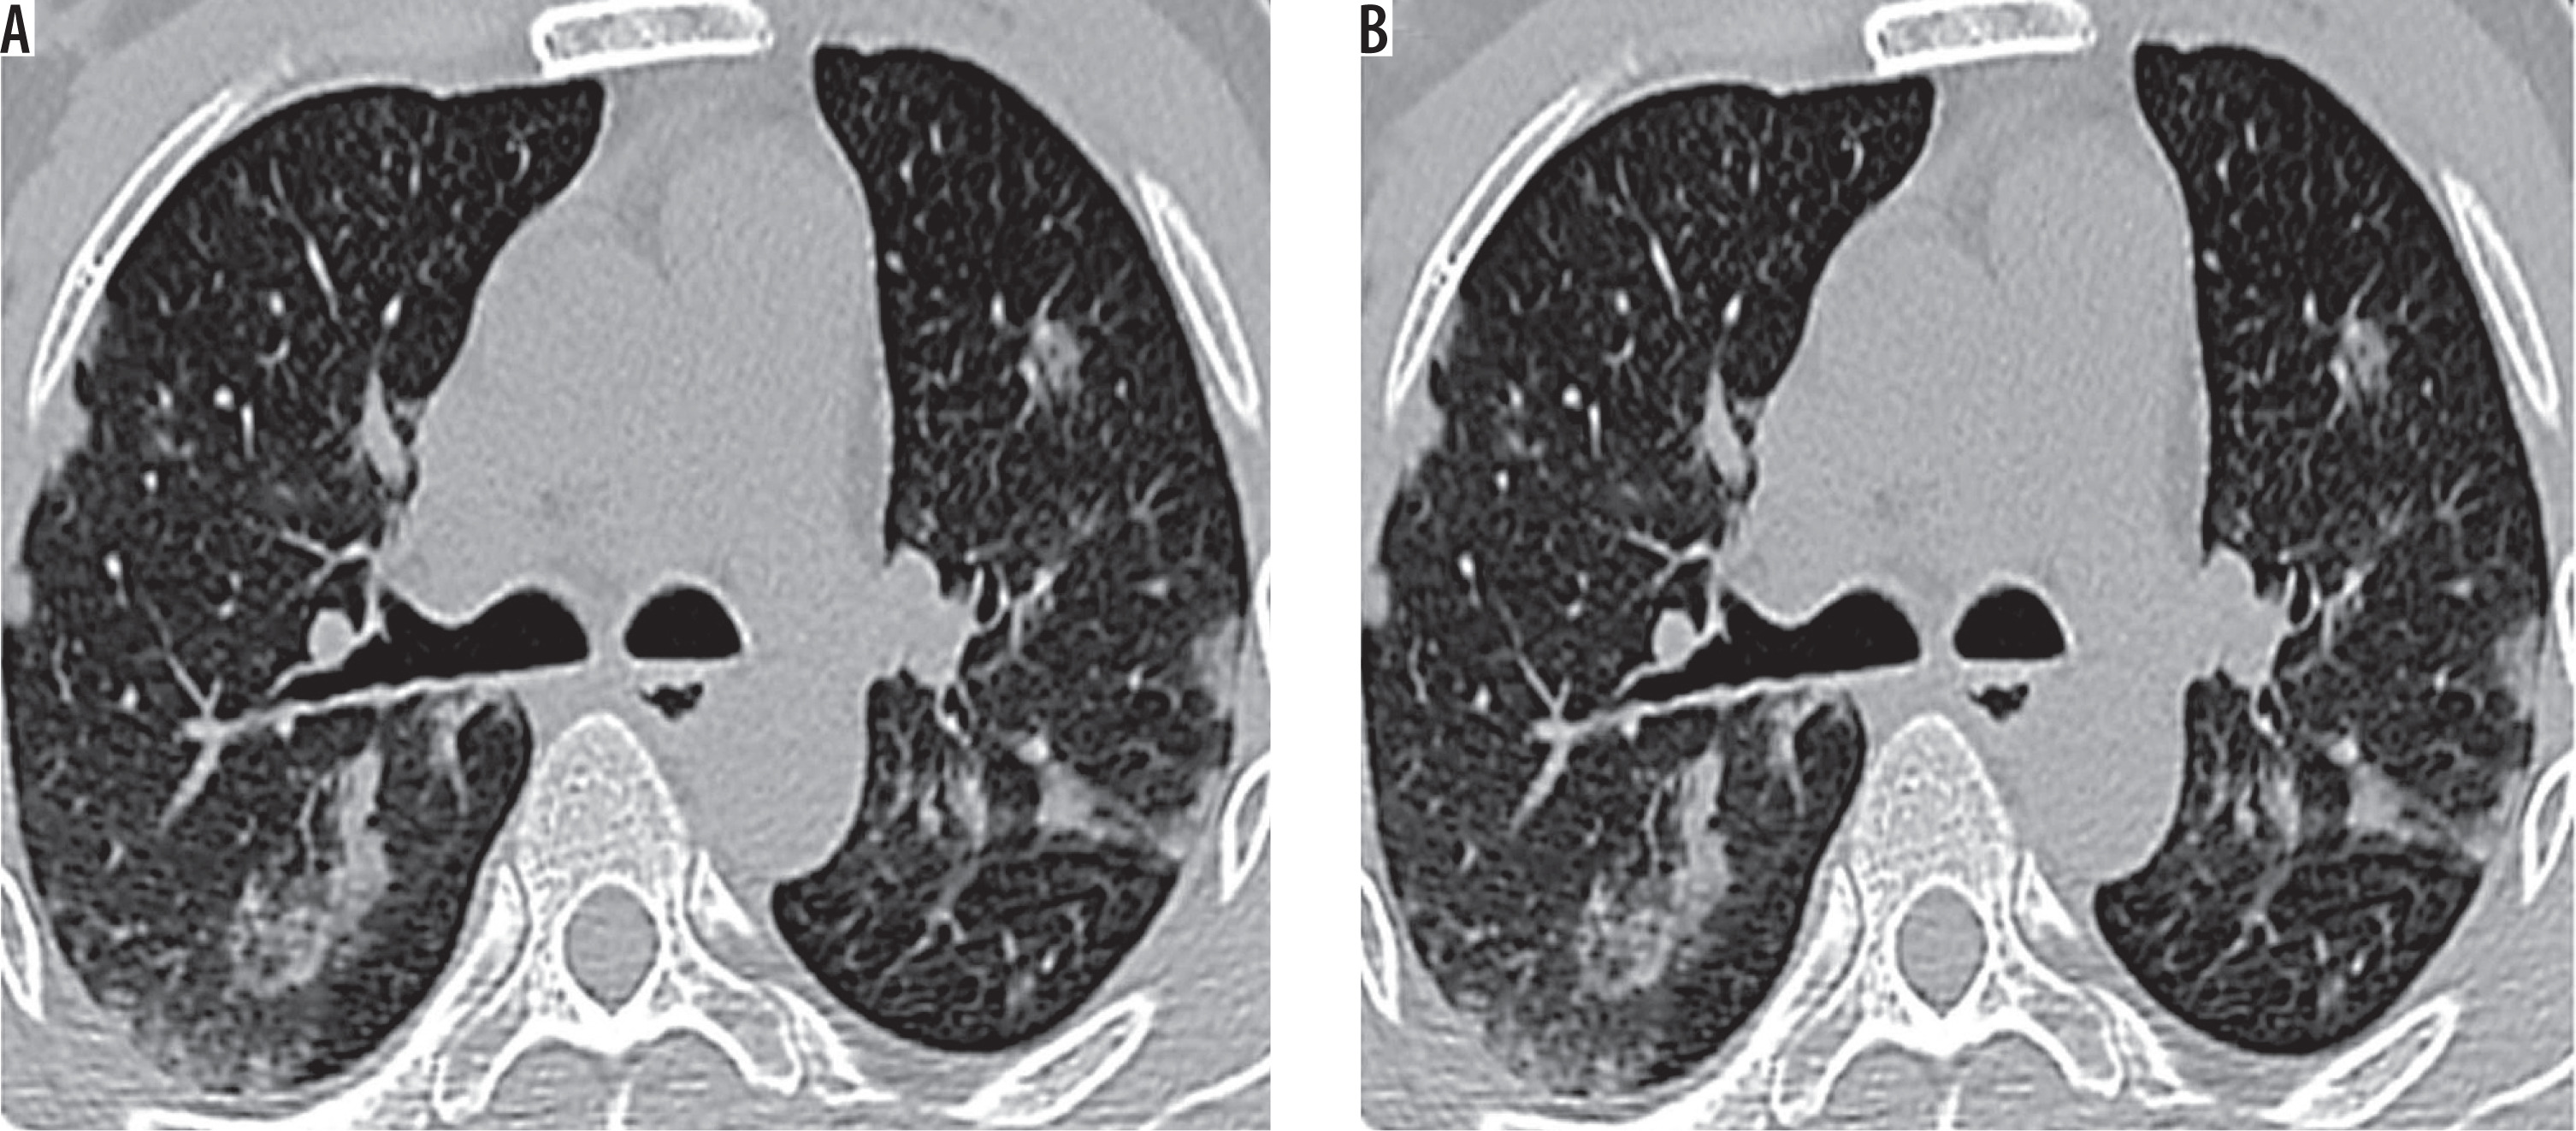

Figure 1

High-resolution computed tomography of lung apices (A, B) in a 66-year-old female with sputum culture positive for acid fast bacilli showing centrilobular nodules, branching nodular, and linear opacities (tree-in-bud pattern) – typical findings of active pulmonary tuberculosis